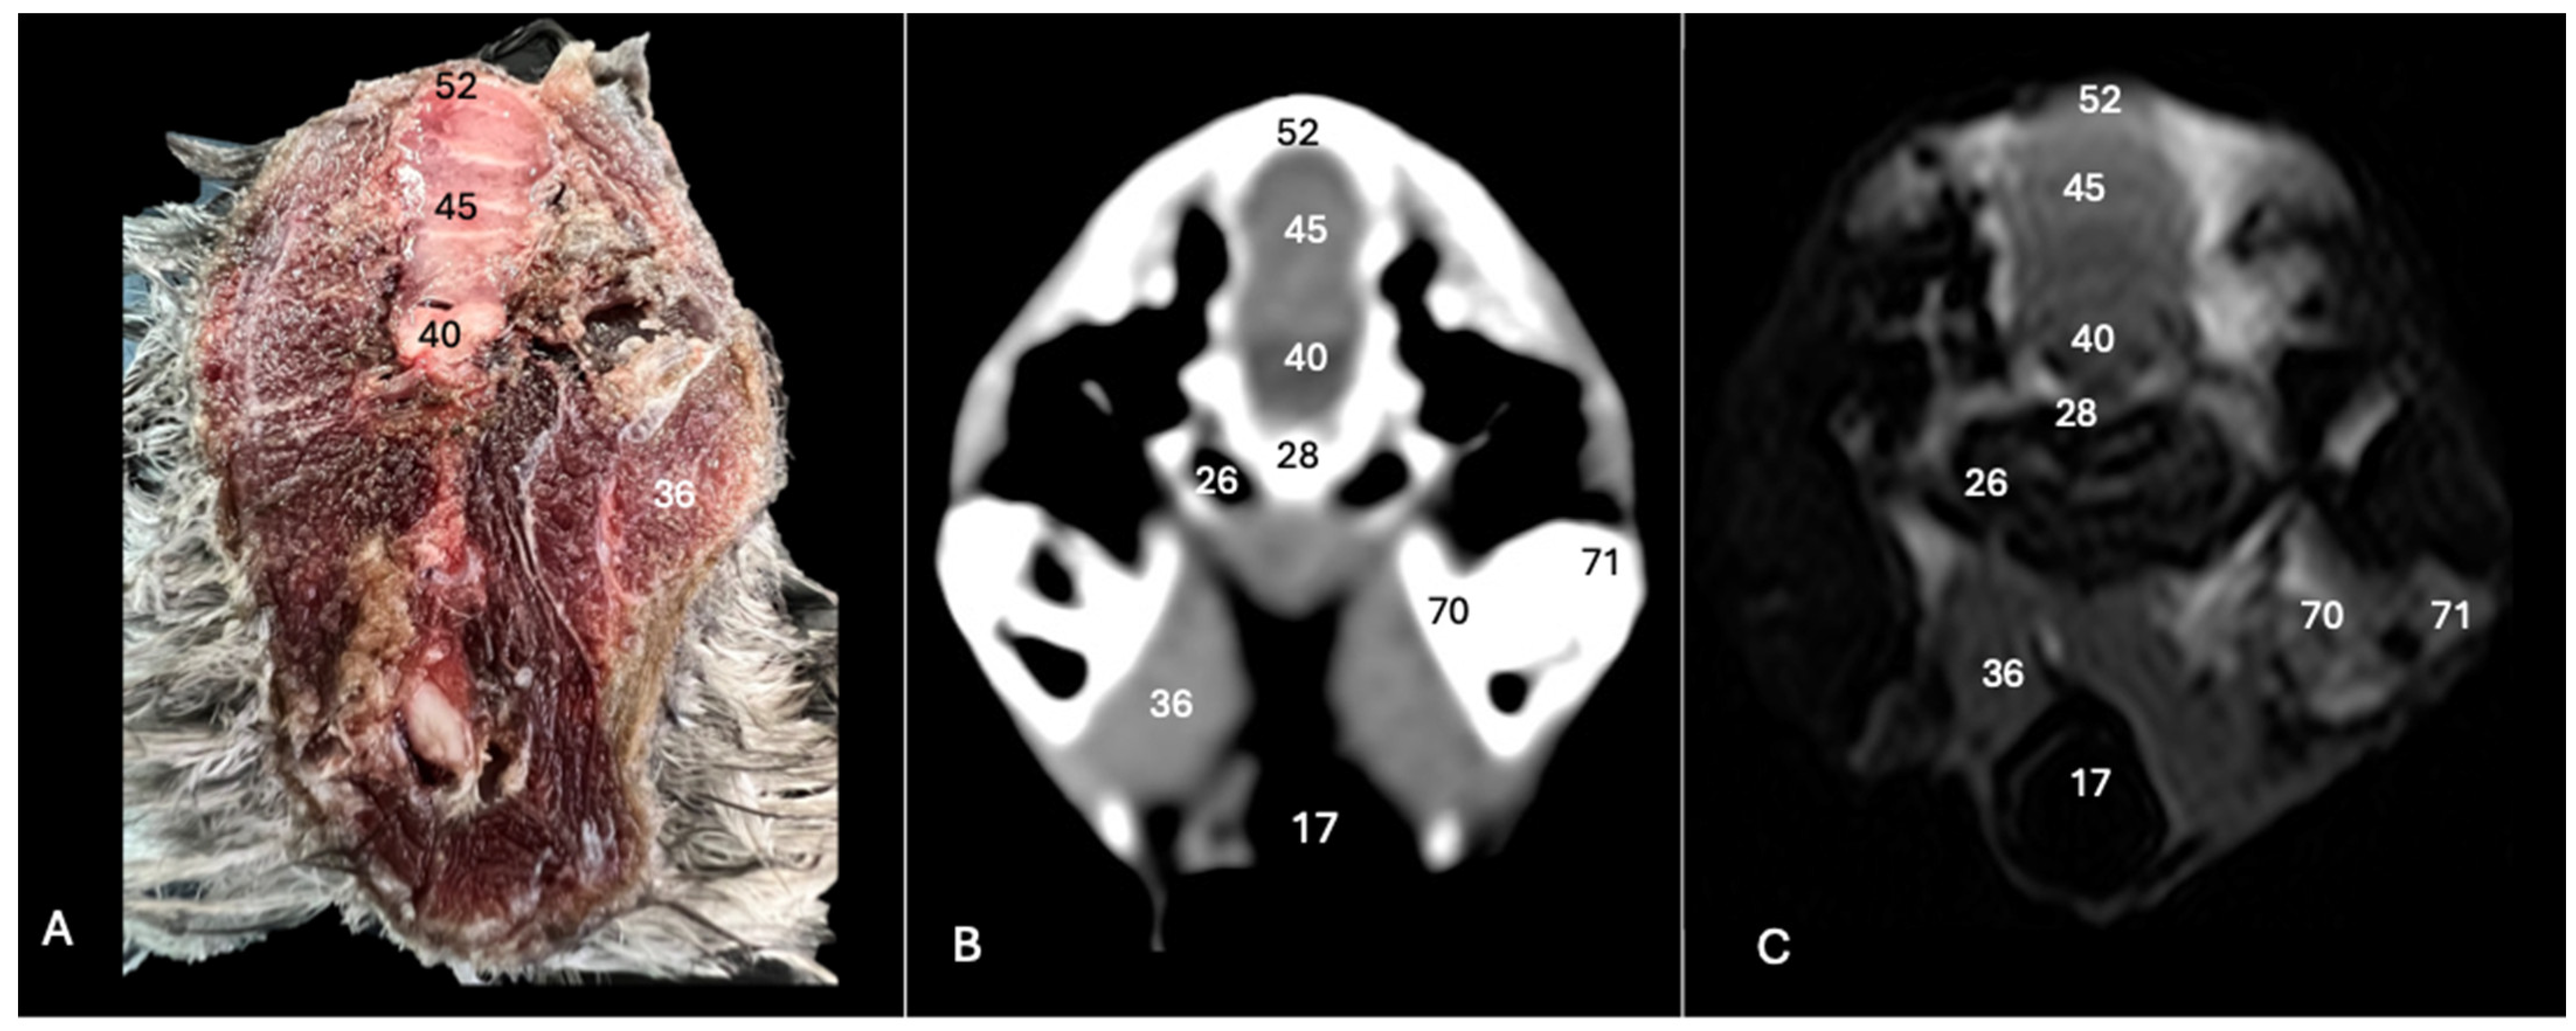

Figure 5. Anatomical cross-section (A), soft tissue CT window (B) and T2-weighted MR (C) transverse images of the Cory’s shearwater head at the level of the cerebellum, corresponding to line IV in Figure 1. 14: Mandible; 17: trachea; 28: basioccipital bone; 32: os parietale; 36: musculus depressor mandibulae pars superficialis plus musculus adductor mandibulae externus; 43: cerebellar hemisphere; 45: cerebellum (body); 46: folia of cerebellum; 47: pons; 70: medial process of the mandible; 71: lateral process of the mandible; 72: quadrate articular fossa.

Figure 6. Anatomical cross-section (A), soft tissue CT window (B) and T2-weighted MR (C) transverse images of the Cory’s shearwater head at the level of the caudal cerebellum, corresponding to line V in Figure 1. 17: Trachea; 26: middle ear; 28: basioccipital bone; 36: depressor mandibulae pars superficialis plus musculus adductor mandibulae externus; 45: cerebellum (body); 40: medulla oblongata; 52: os supraoccipitale; 70: medial process of the mandible; 71: lateral process of the mandible.

These sections also provided insights into other components of the Cory’s shearwater brain. Among these were the mesencephalon, the notable large corpus cerebelli, the internal medullary body characterized by an internal white substance, and caudally, the small paired cerebellar hemispheres, which were identified in the transverse and dorsal sections (illustrated as numbers 45, 80 and 43, respectively, in Figure 5A, Figure 6A, Figure 7A, Figure 8A, Figure 9A and Figure 10A). Additionally, these sections facilitated the identification of the ventral portion of the rhombencephalon, encompassing different components such as the pons and the medulla oblongata, which rested on the basioccipital bone (illustrated as numbers 47 and 40, respectively, in Figure 5A, Figure 6A and Figure 10A).

3.3. Magnetic Resonance Imaging (MRI)

No discernible anatomical differences were observed in the examined shearwaters; however, it is noteworthy that compared to CT, CNS structures were better visualized. Therefore, T2W MR images demonstrated precise alignment with the cranial structures observed in the cadaveric cross-sections, providing a comprehensive view of the CNS and its associated structures. Thus, the examination of Cory’s shearwater brains in transverse, dorsal and sagittal planes allowed the observation of the two telencephalic hemispheres, revealing regions of a moderate-intensity signal (labelled as number 16 in Figure 2C, Figure 3C, Figure 4C, Figure 7C, Figure 8C and Figure 10C). Notably, these imaging planes also facilitated the precise identification of the olfactory bulb, characterized by its small, tapering rostral structure, with moderate and uniform signal intensity (depicted as number 11 in Figure 2C, Figure 7C and Figure 10C). Moreover, the transverse T2W MR images displayed two curved dorsal structures with moderate signal intensity, corresponding with the hyperpallium (corresponding to number 21 in Figure 3C and Figure 4C). The diencephalon, another constituent of the forebrain, exhibited limited differentiation from the adjacent mesencephalon, displaying signals of moderate to low intensity (identified as numbers 49 and 57, respectively, in Figure 10C). Moreover, notable features of the mesencephalon, such as the optic lobe, were perfectly discernible in the transverse and dorsal T2-weighted MRI images, showcasing similar signal characteristics (represented as number 31 in Figure 4C and Figure 8C). Furthermore, other crucial components of the central nervous system, such as the pons and the medulla oblongata, were identifiable across transverse, dorsal and sagittal planes, and characterized by low-intensity signals (depicted as numbers 47 and 40, respectively, in Figure 5C, Figure 6C and Figure 10C). Adjacent to the brain stem, the corpus cerebellum and the small paired cerebellar hemispheres displayed indistinct areas of hypo- and moderate-intensity signals (shown as numbers 45 and 43, respectively, in Figure 5C, Figure 6C, Figure 7C, Figure 8C, Figure 9C and Figure 10C).